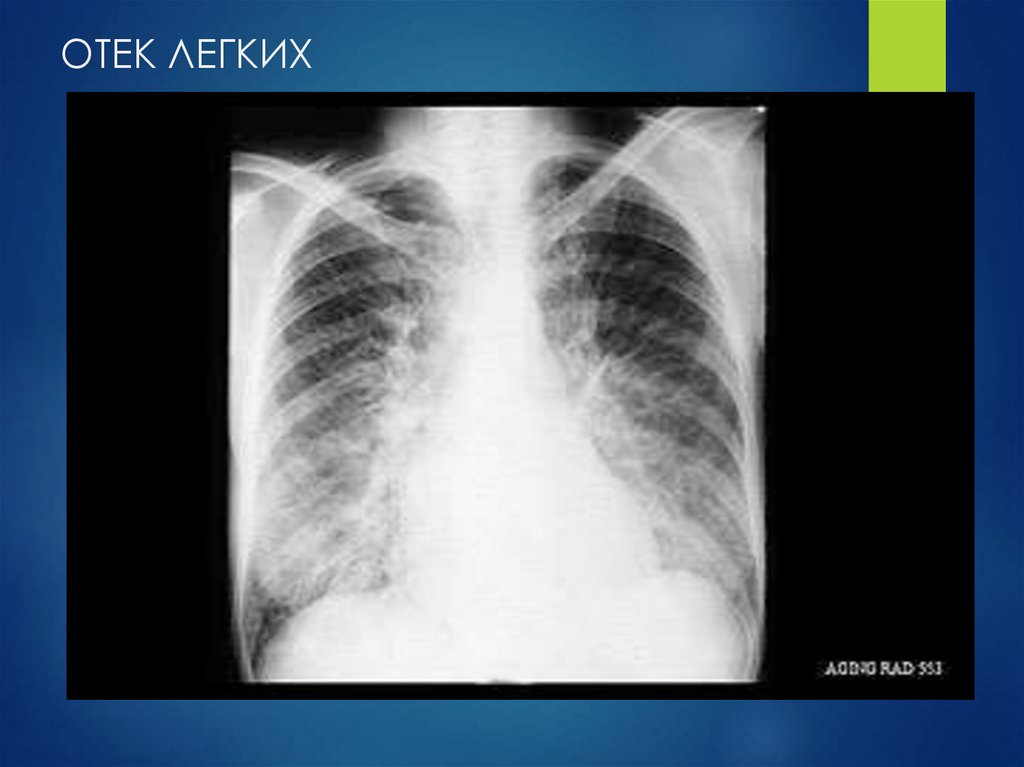

ОТЕК ЛЕГКИХ